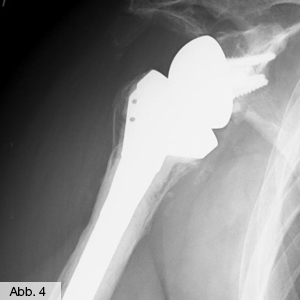

Wenn aufgrund eines Rotatorenmanschettenrisses starke Beschwerden bestehen, eine Naht der Sehnen aber nicht mehr möglich ist, können Schmerzfreiheit und Funktion dennoch wiederhergestellt werden: es ist dann der Einsatz einer inversen Prothese möglich. Hierdurch werden die Hebelverhältnisse am Schultergelenk dergestalt verändert, dass die Schulterfunktion mit dem verbliebenen Deltamuskel bewerkstelligt werden kann. Falls dieser Eingriff dem Patienten zu groß erscheint oder aus medizinischen Gründen nicht möglich ist, besteht als letztes die Möglichkeit, arthroskopisch ein "Schulterkissen" einzusetzen. Durch diesen einfachen Eingriff können die Schmerzen beseitigt und die Funktion teilweise wiederhergestellt werden. Das Kissen wird allerdings vom Körper innerhalb von zwei Jahren abgebaut, so dass der Eingriff bei erneuten Beschwerden wiederholt werden muss.

Zur Behandlung der Omarthrose bietet die Klinik für Orthopädie ein breites Spektrum an therapeutischen Maßnahmen. Bei auftretenden Krankheitssymptomen werden die Beschwerden in der Schulter zunächst konservativ mit Medikamenten, physikalischen Maßnahmen oder lokalen Injektionen behandelt. Ist die degenerative Erkrankung des Schultergelenks bereits zu weit fortgeschritten, besteht die Möglichkeit, ein künstliches Schultergelenk zu implantieren. Mit der Endoprothese werden die Teile des Gelenks ersetzt, die durch die Erkrankung verschlissen sind. Bei der Wahl der Prothese berücksichtigen unsere Fachärzte, bei jedem Patienten so viel Knochensubstanz wie möglich zu erhalten. So steht neben Voll- und Teilprothesen auch die stiellose Kurzprothese zur Verfügung. Das Implantat erhält den Knochen im Hals- und Stielbereich des Oberarms und wird nur mit einem kurzen Stiel im Knochen verankert. Es kann auch mit einem Pfannenersatz im Schulterblatt kombiniert werden und wird vorzugsweise bei jüngeren Patienten eingesetzt, um für eine eventuell spätere Revisionsoperation möglichst viel Knochensubstanz zu erhalten. Bei der Teil- oder Vollendoprothese hingegen wird der gesamte Oberarmkopf entfernt und durch eine Schaftprothese ersetzt, die wahlweise mit einer künstlichen Schulterpfanne kombiniert wird – zumeist in zementfreier Technik. Bei komplizierteren Fällen verwenden wir mehrteilige "modulare" Prothesen. Durch ein Halsstück, das auf dem Schaft befestigt wird, lässt sich der Oberarmwinkel individuell einstellen. Darauf wird schließlich das in verschiedenen Größen erhältliche Kopfteil fixiert – so kann das Implantat individuell an die Anatomie des Patienten angepasst werden.

Bild Orthopädie Schulter Kurzschaftprothese

Bild Orthopädie Schulter Inverse Prothese

Für den Fall, dass die Omarthrose mit starken Sehnendefekten der Rotatorenmanschette verbunden ist, kommt anstelle einer herkömmlichen Vollprothese eine so genannte inverse Schulterprothese zum Einsatz: Um die Hebelverhältnisse am Schultergelenk zu verändern, muss die Gelenkanatomie mit Hilfe des besonderen Prothesenmodells umgekehrt (invers) werden. So wird der Prothesenkopf statt auf dem Oberarmknochen auf der Gelenkpfanne verankert – dadurch unterstützt bzw. ersetzt der Deltamuskel die fehlende Funktion der Rotatorenmanschette.